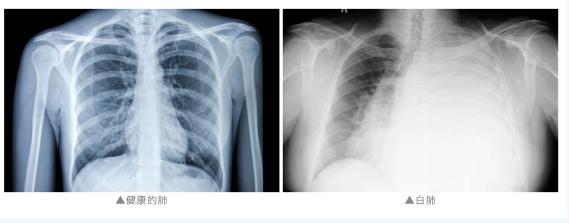

經(jīng)CT檢查 因肺部感染多種病毒 陳女士已經(jīng)發(fā)展成重癥肺炎 肺功能基本喪失 嚴(yán)重呼吸衰竭 隨時(shí)有生命危險(xiǎn) 江都人民醫(yī)院重癥醫(yī)學(xué)科主任 陳齊紅介紹: “兩個(gè)肺都是白的, 發(fā)現(xiàn)的時(shí)候是甲流, 而且是混合感染。” 原來(lái),陳女士 得流感后會(huì)發(fā)展成肺炎嗎? 醫(yī)生表示 無(wú)論是甲流還是乙流 嚴(yán)重的病人都可能出現(xiàn) 比如肺炎、心肌炎 或神經(jīng)系統(tǒng)的并發(fā)癥的表現(xiàn) 由于大多數(shù)病人就診較早 因此發(fā)生合并肺炎的病人并不多 比例在10%以下 甲流和乙流會(huì)同時(shí)感染嗎? 近期 乙流引發(fā)公眾關(guān)注 醫(yī)生表示,確實(shí)遇到過(guò) 同時(shí)感染甲流和乙流的病人 以及感染甲流后又感染乙流的病人 這是因?yàn)?/span> 甲流和乙流是流感的兩種亞型 二者存在一定差異 因此感染甲流并不能對(duì)乙流 產(chǎn)生完全的交叉免疫 感染甲流或乙流后 如果患者體質(zhì)相對(duì)弱 依然有可能感染 另一種亞型的流感病毒